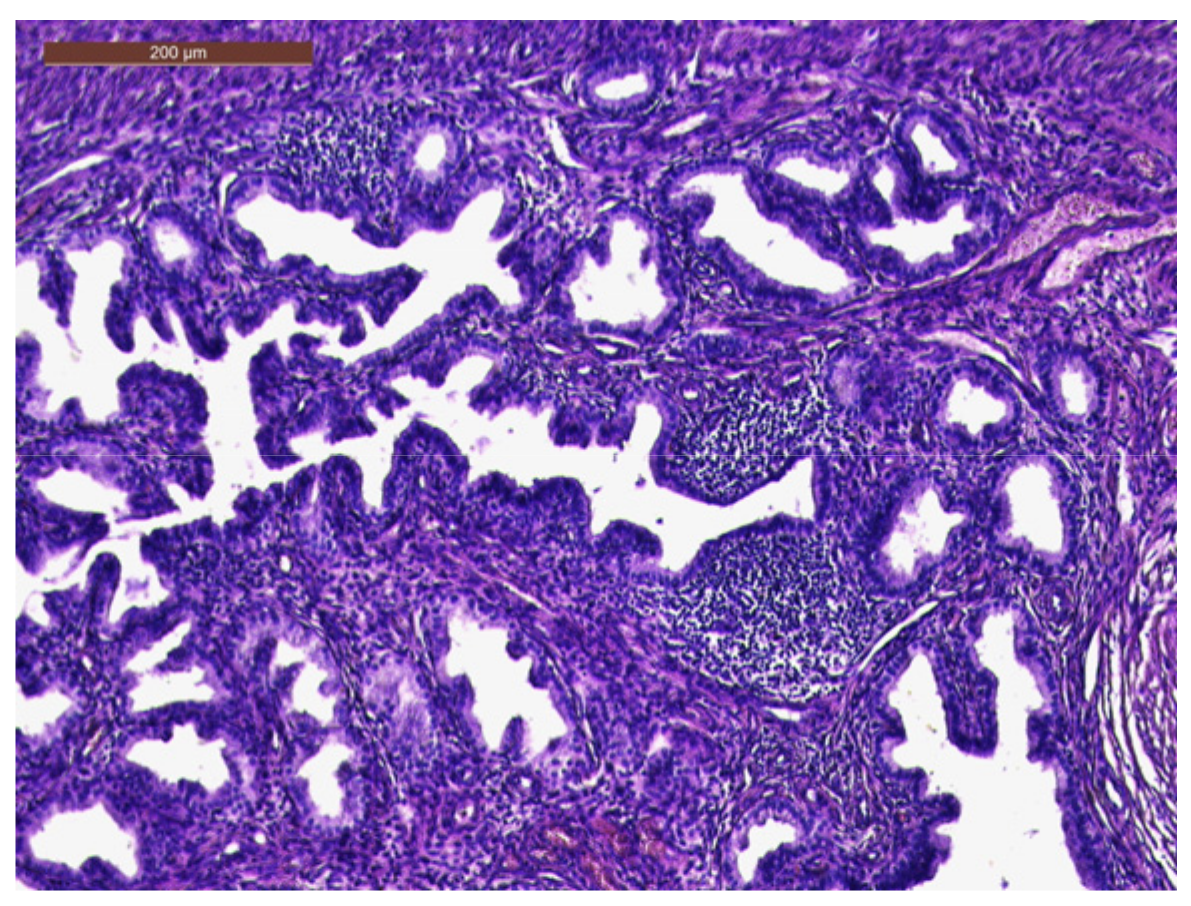

The histopathological exam revealed the tissue fragments to be sufficiently delimited by a thin layer of the endometrium composed of a biphasic stromal and glandular proliferation and represented by cellular stroma with edematous areas with thin blood vessels interspersed with thick bundles of smooth muscular fibers that included irregularly contoured secretory endometrial glands (Figure 4 and Figure 5), organized in hyperplastic lobular areas, and lined by the simple and pseudostratified epithelium with hyperchromatic nuclei (Figure 6), eosinophilic metaplasia, and a tendency for squamous differentiation.

Our microscopic findings are consistent with the following histopathological characteristics that define the atypical polypoid adenomyoma: a well-circumscribed biphasic tumor composed of endometrioid glands with a complex or lobular histoarchitecture, squamous morular metaplasia, and sometimes cytologic atypia, interspersed with a fibromyomatous stroma, which may present myxoid change.

Figure 6. Hyperplastic endometrial glands, with irregular lumen; focal pseudostratified epithelium; and hyperchromatic nuclei (HE × 20).